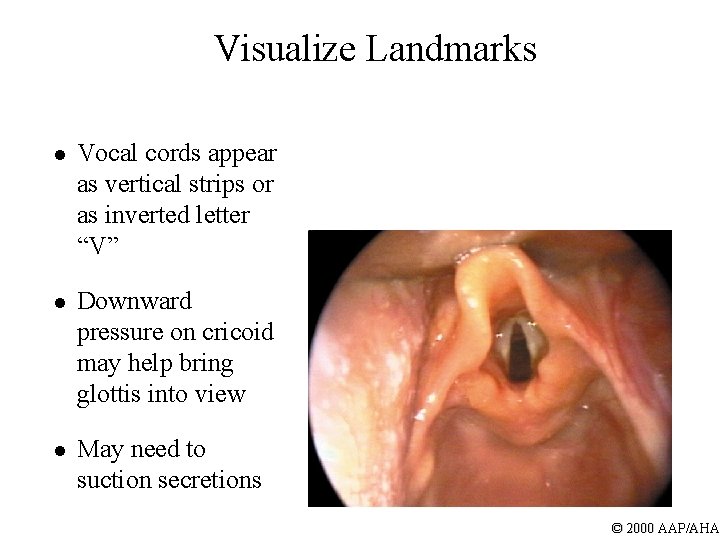

Visualize Landmarks l Vocal cords appear as vertical strips or as inverted letter “V” l Downward pressure on cricoid may help bring glottis into view l May need to suction secretions © 2000 AAP/AHA